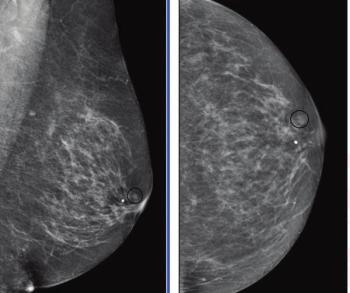

In multiple mammography datasets with the original radiologist-detected abnormality removed, deep learning detection of breast cancer had an average area under the curve (AUC) of 87 percent and an accuracy rate of 83 percent, according to research presented at the recent Society for Imaging Informatics in Medicine (SIIM) conference.